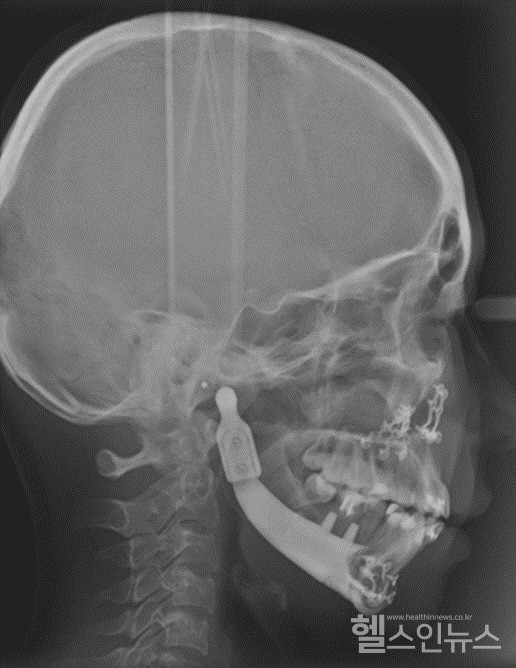

3D프린팅으로제조된환자맞춤형인공하악골X레이사진

회사에 따르면 해당 기술은 하악골의 결손 부위에 삽입되는 환자 맞춤형 하악골 임플란트이다. 개인 맞춤형 3D 프린팅 기술을 이용하여 손쉽고 빠르게 제작할 수 있으며, 아래턱뿐만 아니라 턱뼈와 함께 손실된 치아를 복원하는 기술도 동시에 적용 가능하다.

이번에 미국 특허로 등록된 ‘하악골 결손 부위에 삽입되는 환자 맞춤형 하악골 임플란트(영문명: Patient-tailored mandibular implants and methods for manufacturing the same)’는 사고로 인한 외상 혹은 구강암 등의 질환으로 인해 아래턱뼈가 결손된 환자에게 본인의 구강구조와 일치하는 맞춤형 인공 턱뼈를 제공할 수 있으며, 추후 치과용 임플란트를 식립할 수 있으며 치아의 기능까지 회복할 수 있어, 심미적, 기능적 복원이 가능하다는 장점이 있다고 회사측은 설명했다.